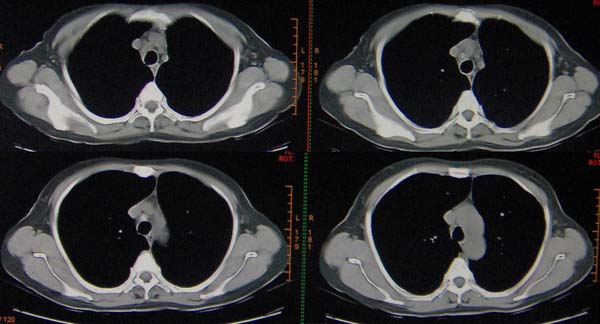

标题: CT9509:女,50岁,咳嗽,发热,38度, [打印本页]

标题: CT9509:女,50岁,咳嗽,发热,38度,

与x2653同一病人:http://www.radida.com/bbs/forum.php?mod=viewthread&tid=28727